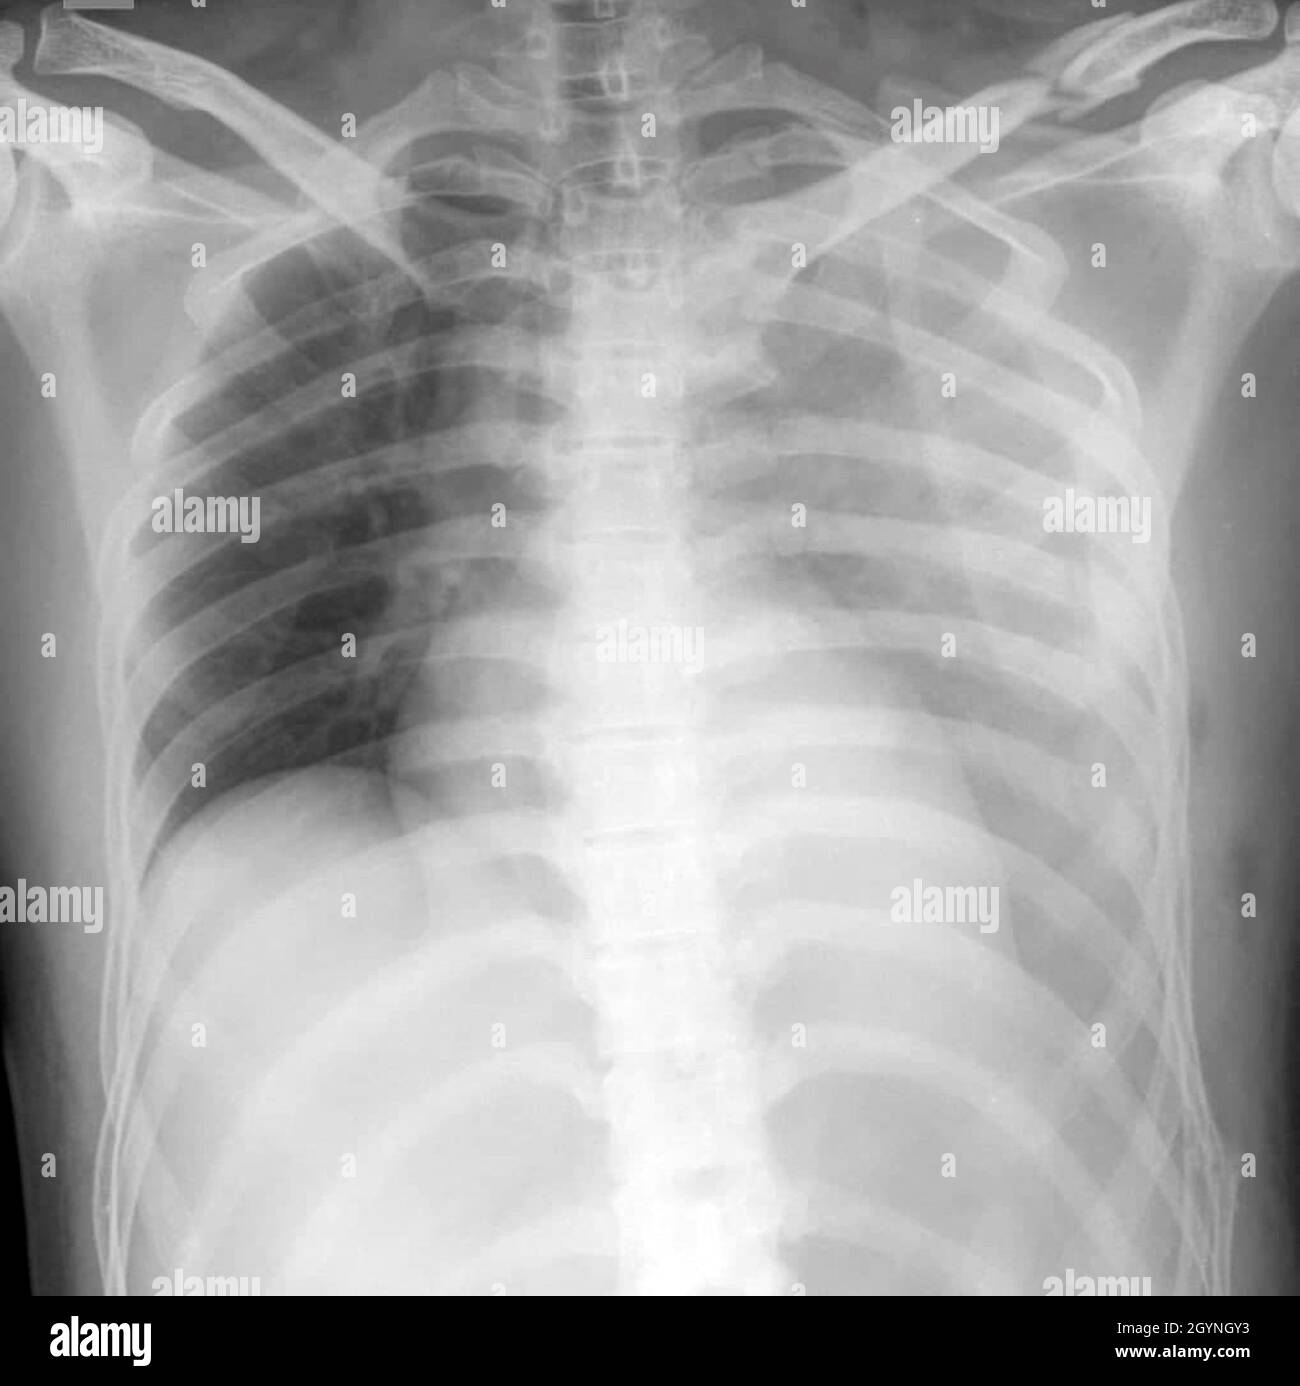

Radiopaedia.org provides detailed information on hemothorax, a condition where blood accumulates in the chest cavity. The clinical findings in such patients include respiratory distress. Signs of hemothorax at radiography include blunting of the costophrenic angle, obscuration of the hemidiaphragm, homogeneous opacity of the hemithorax, fluid within the interlobar fissures, or an apical cap. Upright chest radiography is the ideal primary diagnostic study in the evaluation of hemothorax. L’hémothorax est une accumulation de sang entre le poumon et la paroi thoracique. When a chest tube is placed, the fluid may be evaluated to confirm the presence of blood in the pleural cavity and further look for possible causes. Hemothorax is a collection of blood in the space between the visceral and parietal pleura (pleural space). Les personnes peuvent se sentir étourdies et essoufflées,. Additional imaging studies, such as ultrasonography (us) and. A chest ct or further testing may then be considered.

Chest Radiograph Showing A Massive Right Hemothorax D vrogue.co Hemothorax X-Ray When a chest tube is placed, the fluid may be evaluated to confirm the presence of blood in the pleural cavity and further look for possible causes. Hemothorax is a collection of blood in the space between the visceral and parietal pleura (pleural space). Upright chest radiography is the ideal primary diagnostic study in the evaluation of hemothorax. The clinical. Hemothorax X-Ray.